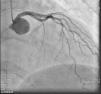

On admission the pain was decreasing; the physical examination was unremarkable, the electrocardiogram showed sinus rhythm, with negative T waves in the inferior leads, and troponin I was positive. The pain eventually disappeared after intravenous nitrates, and she was admitted to the coronary care unit. She underwent coronary angiography (Figure 1, Video 2), which revealed a spontaneous dissection of the posterior descending artery, with TIMI 2 flow, some posterolateral branches visualized from intercoronary collaterals, and severe vasospasm of the proximal right coronary artery (RCA), which reproduced the pain, relieved after intracoronary nitrates. No other unequivocal coronary lesions were noted, although a long dissection of the left anterior descending artery with intact intima cannot be excluded (Online Figure 2). It was decided not to perform percutaneous coronary intervention (PCI), and she was kept in the ward anticoagulated with subcutaneous enoxaparin (1 mg/kg twice daily), with dual antiplatelet therapy and a calcium channel blocker. Screening for autoimmune disease was negative. There were no events during hospitalization and she was scheduled for an angiographic review a week later, which showed progression of the dissection, with a wider false lumen (Figure 2, Video 3). Pain recurred during the procedure and a dissection was noted in a posterolateral branch. It was decided to perform PCI, and two bioabsorbable vascular scaffolds (BVS) were implanted in the PDA, guided by optical coherence tomography (OCT) coregistered with angiography. A third BVS was implanted in the distal RCA due to proximal progression of the dissection. A bare-metal stent was also implanted in the ostial RCA due to a traumatic dissection induced by the guiding catheter. Comparison of the images from angiography and OCT reveals a discrepancy in total (false plus true) diameter in the distal RCA (Figure 3, Video 4). After the procedure the patient was asymptomatic, although with a significant residual dissection in the RCA and posterolateral branch (Video 5). Anticoagulation was suspended and she was discharged five days later, with no further episodes of chest pain. Four months after this episode, she has had no recurrence of pain and is asymptomatic.